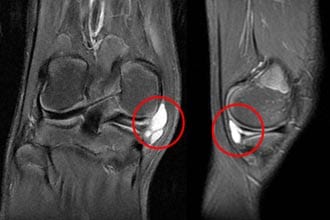

- параменисковая киста. Это своего рода заболевание мениска, в случае его разрыва появляются образования разной величины, опухоль большого размера может переходить на связки колена. Диагностирование и пальпация при данном типе заболевания не представляет сложности. Лечение в домашних условиях народными средствами невозможно. Тут требуется хирургическое вмешательство, которого можно избежать только в случае быстрого обращения к врачу. При правильном ведении физиотерапевтических мероприятий данной ситуации можно не допустить, и сустав будет работать нормально;